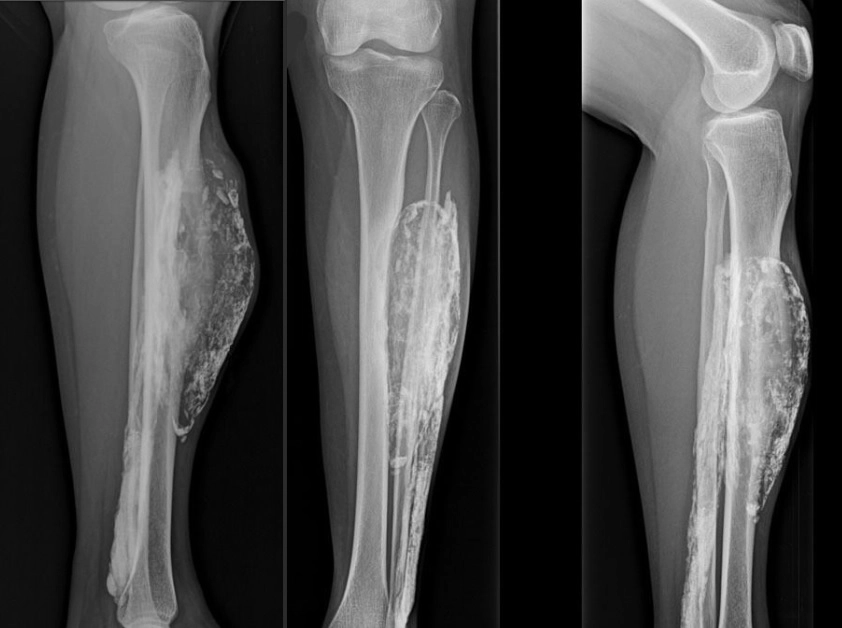

The painless mass had become noticeable 10 years earlier, and on an X-ray it looked like an enlarged cavity wrapped in a tough, calcified membrane, resembling an eggshell. It ultimately grew so large that it broke through the woman's skin. Doctors surgically removed the mass, and the wound completely healed by one month after the surgery, they wrote in their report, published June 16 in the Journal of Medical Case Reports.

The result is usually a firm, hard, palpable mass that can be examined using X-ray or MRI scans. [Image of the mass]